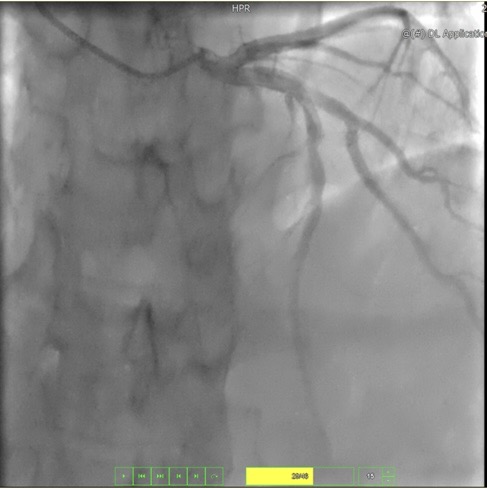

由于患者心功能极差(心脏射血分数仅有EF 0.34,患者入院时心脏彩超正常人大于0.5),入院后高峰主任立即组织科室进行讨论,就周先生目前的心脏状态,制定了详细的抗心衰诊疗方案,在纠正心功能的同时,积极完善术前相关检查,发现周先生不仅心功能极差,还合并永久性心房颤动,即心房由于老化、炎症等原因发生了快速而无规律的颤动,无法正常收缩舒张,心脏泵血功能下降,心房内尤其是左心耳,由于血液瘀滞而容易形成血栓,一旦脱落可引发脑卒中。另外,冠状动脉造影还提示前降支50%狭窄,这无疑是雪上加霜。